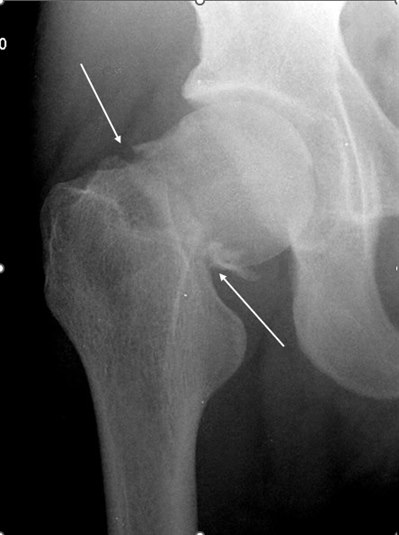

- Badanie rentgenowskie

- wybór projekcji w zależności od przypuszczalnego obrazu klinicznego.

- Uwaga: brak korelacji między obrazem radiologicznym choroby zwyrodnieniowej stawów biodrowych a nasileniem objawów!10

- Nie wykonywać zdjęcia rentgenowskiego w celu monitorowania leczenia!